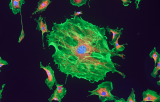

Le carcinome des cellules rénales (CCR), également appelé hypernéphrome, adénocarcinome rénal ou cancer du rein, est un cancer du rein qui prend naissance dans la paroi du tubule proximal convoluté, une partie des très petits tubes du rein qui transportent l'urine primaire. Le CCR est le type de cancer du rein le plus fréquent chez l'adulte, le carcinome des cellules rénales (CCR) a le taux de mortalité le plus élevé des cancers génito-urinaires et l'incidence du CCR a augmenté régulièrement. S'il est détecté à un stade précoce, le CCR peut être soigné par chirurgie, bien qu'une minorité de personnes soit exposée à un risque de récidive. Le CCR est un cancer à croissance rapide qui se propage souvent aux poumons et aux organes environnants. Les symptômes peuvent comprendre une hématurie, des douleurs de flanc, une masse palpable et une fièvre d'origine inconnue. Cependant, les symptômes sont souvent absents, de sorte que le diagnostic est généralement suspecté sur la base de découvertes fortuites.